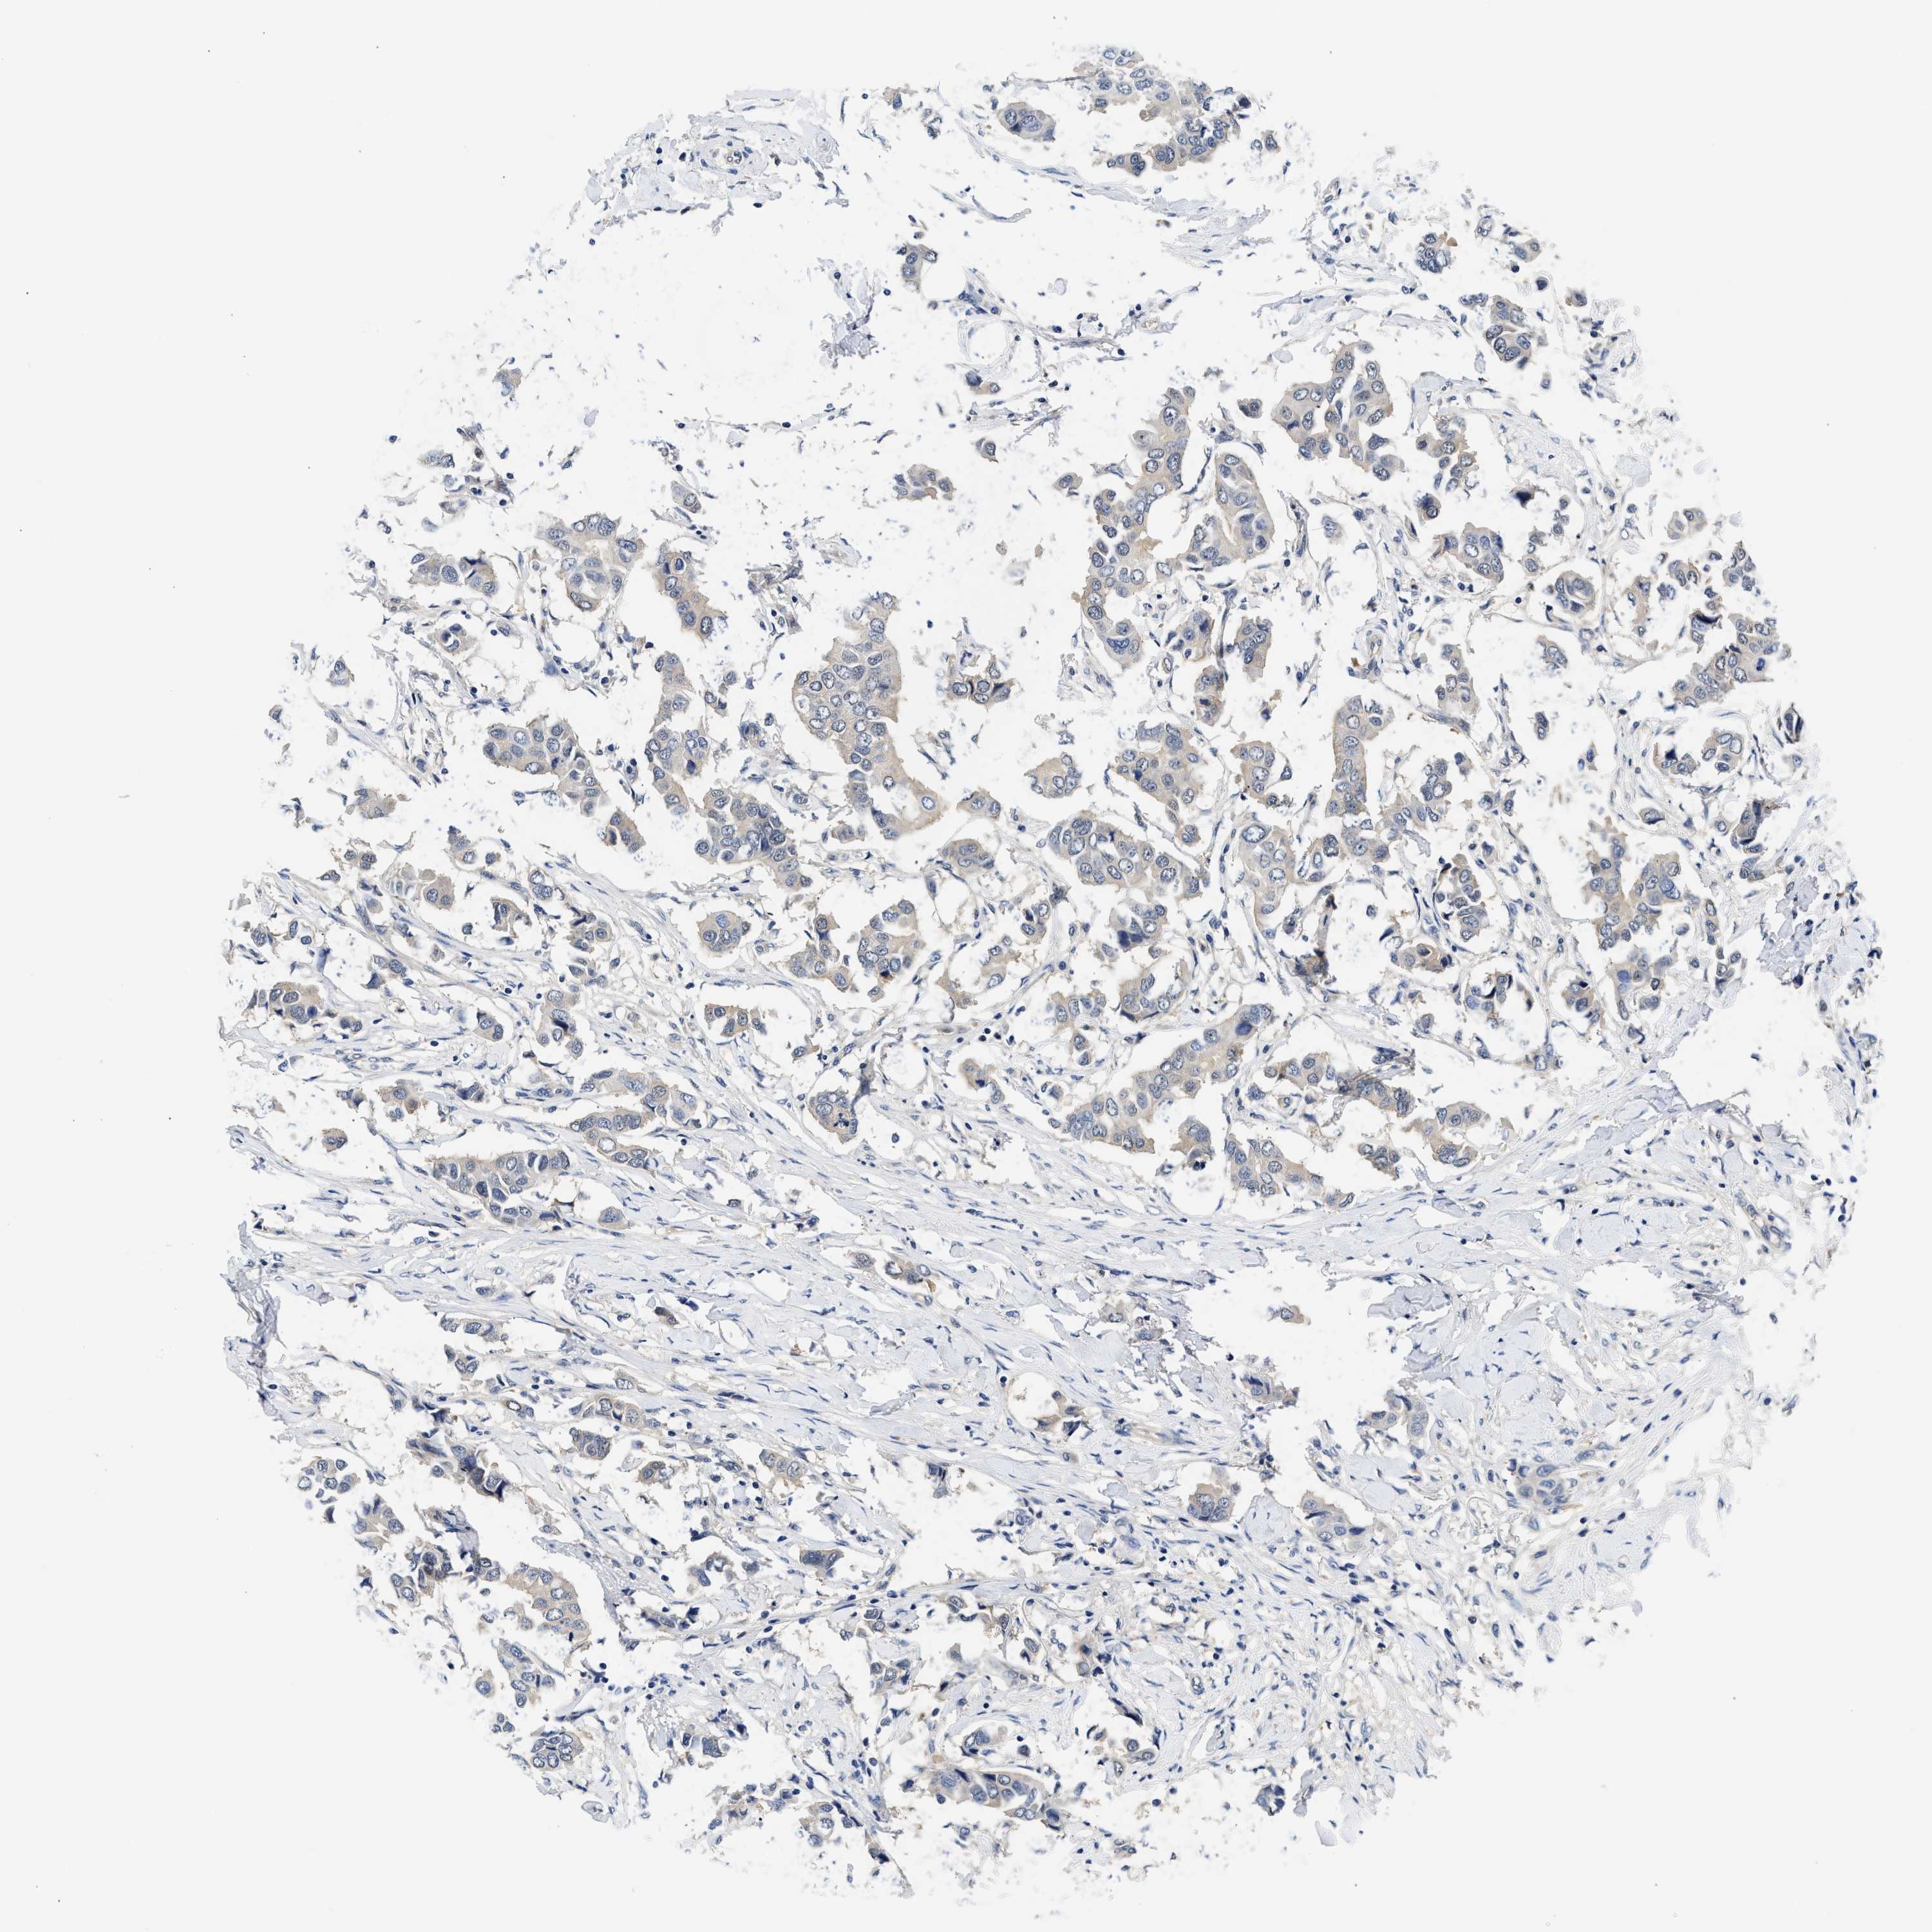

BRCA TCGA BRCA VALIDATION PROTEIN EXPRESSION